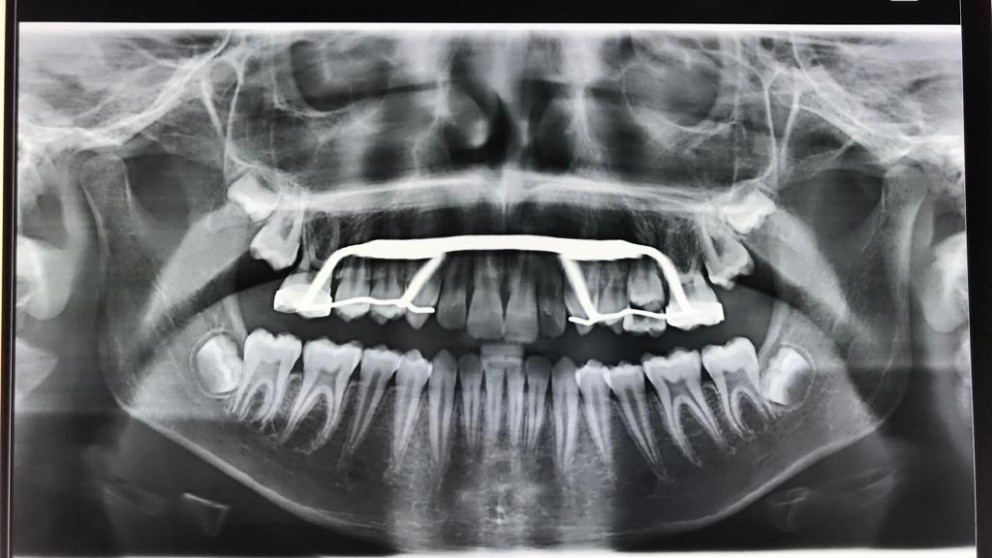

L'espansore è un dispositivo ortodontico usato per correggere il difetto del palato stretto. Viene fissato sui secondi premolari da latte o sui primi molari permanenti tramite una vite centrale che deve essere regolarmente attivata con una chiavetta per un periodo stabilito dall'ortodontista. Ha la funzione di espandere e allargare il palato.

Il palato stretto è uno dei disturbi più comuni che si riscontra nei bambini e consiste nella mancanza di spazio adeguato per far uscire in posizione corretta i denti permanenti. Ciò provoca un sovraffollamento dentale. Lo sapevi già?!